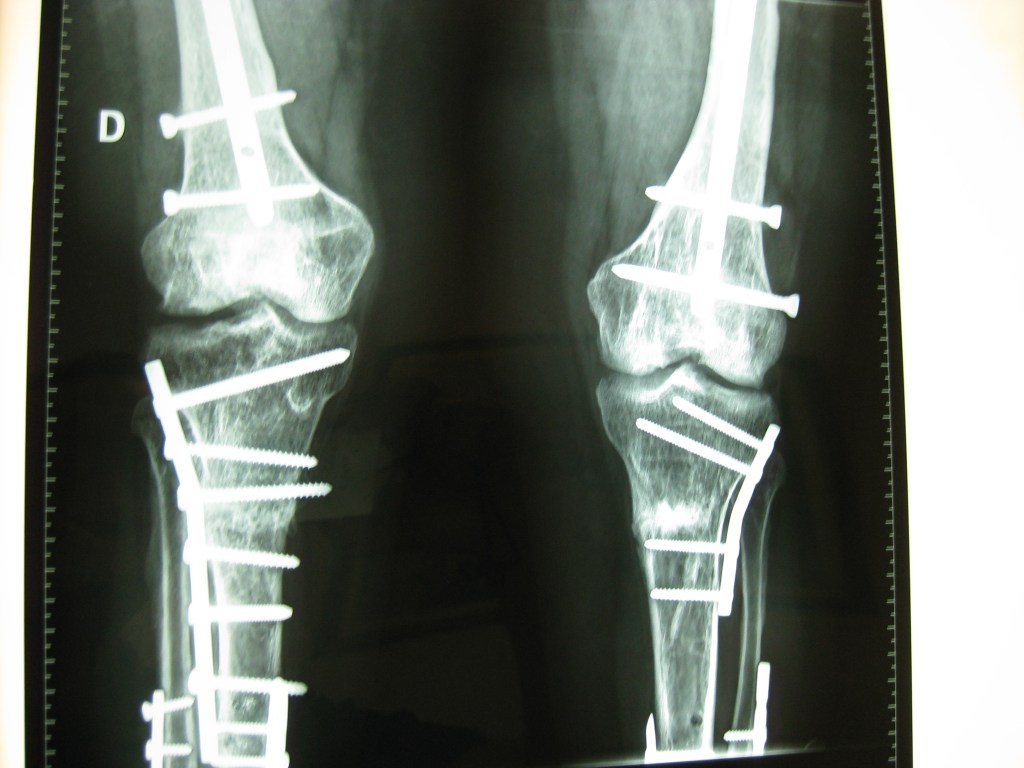

Deformidad grave de pierna con acortamiento oseo e infección

Luego de 10 años de cirugías en distintos centros del país , mi única opción era realizarme una amputación

Luego de consultar con el Dr Dratewka y su Equipo , me explicaron la necesidad de varias cirugías en etapas para tratar mi infección , corregir mi pie y devolver el largo de mi pierna

No tengo palabras para lo que me hicieron y ayudaron ,me sentí acompañada en todo momento y ahora puedo decir que no duden en hacer una consulta si tienen dudas sobres su problema